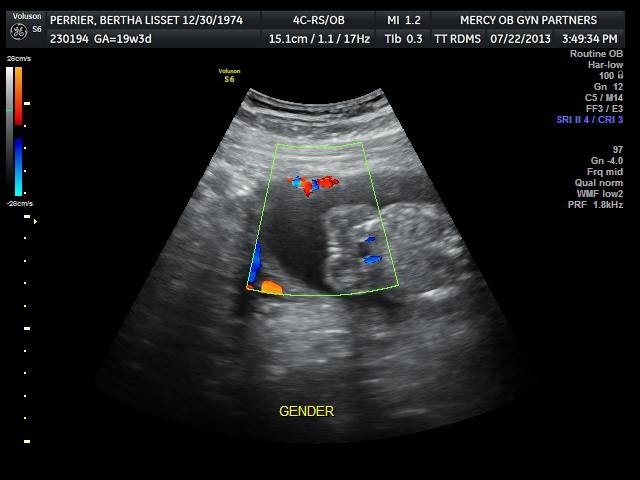

I need more opinions the dr look at the pics and said maybe girl what do u think??

Can't really tell what I'm looking at. But I don't see a penis and scrotum, so he's probably right! Congrats!

It's not my favorite angle as it can be deceiving but what I see looks girly. Congrats!

Prolly a girl. I see lines.